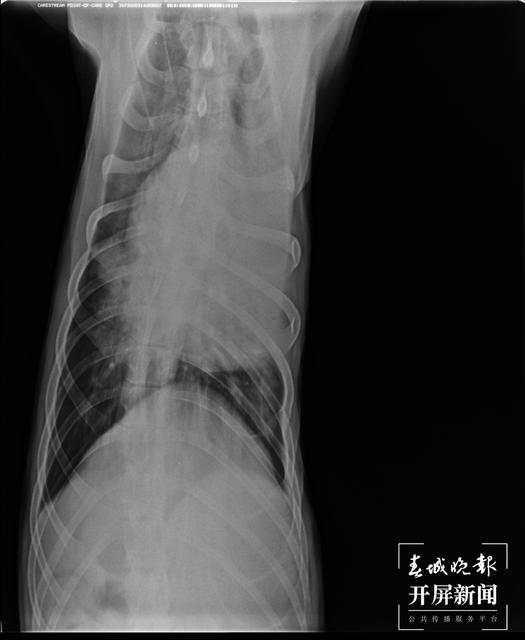

2月19日,CT显示肺部水肿严重。(受访者供图)